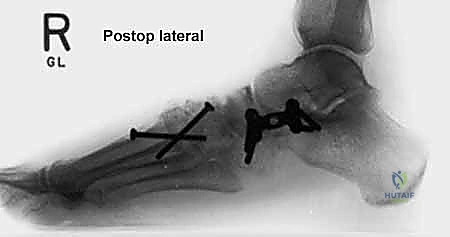

إطالة العمود الجانبي للقدم، أو قطع عظم إيفانز، هو إجراء جراحي حيوي لتصحيح تشوه القدم المسطحة المكتسبة الناتج عن قصور الوتر الظنبوبي الخلفي. يهدف إلى استعادة قوس القدم وتخفيف الألم وتحسين وظيفة القدم، ويتم على يد خبراء مثل الأستاذ الدكتور محمد هطيف.

في هذا الدليل المرجعي، سنسلط الضوء بشكل مكثف على الحل الجراحي المتقدم والفعال المعروف باسم إطالة العمود الجانبي للقدم (Lateral Column Lengthening)، وتحديداً التقنية الجراحية الدقيقة المسماة "قطع عظم إيفانز" (Evans Osteotomy). يُعد هذا الإجراء حجر الزاوية في استعادة الميكانيكا الحيوية الطبيعية للقدم، وإعادة بناء القوس المنهار، وتخفيف الألم بشكل دائم.

* الأشعة السينية (X-rays) مع تحمل الوزن: ضرورية لتقييم درجة انهيار القوس وزوايا العظام (مثل زاوية تالونافيكولار Meary's Angle).